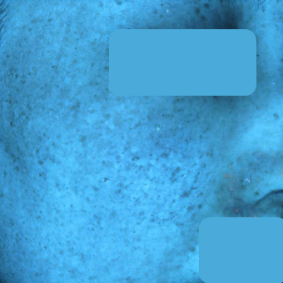

30대 여성 색소 치료 3개월 후기

치료 전 25.08.06

치료 후 25.10.23

현재 피부고민 : 출산 후 짙어진 잡티 및 색소, 피부톤 불균형

- UV 촬영상: 색소 밀도가 전반적으로 감소하며, 멜라닌 분포가 고르게 정리되었습니다.

- NL(일반광) 촬영: 눈에 띄던 잡티와 색소가 옅어지고, 피부톤이 밝고 균일해진 모습이 확인되었습니다.

- 육안상으로도 투명감과 맑은 윤기가 회복되었으며, 시술 후 자극이나 홍반 없이 안정적인 회복을 보였습니다.